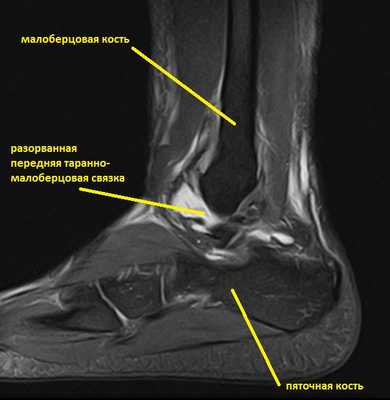

Ниже представлены срезы МРТ в которых наглядно показано расположение повреждённых связочных структур.

Данные повреждения практически в 100 % случаев пропускаются при первичном обращении в травмпункт. При несвоевременном или неадекватном лечении нестабильность голеностопного сустава приводит к разрушению суставного хряща, выраженной боли, деформации, и в конечном счёте к полной утрате функции опоры и ходьбы. В зависимости от того какие связки разорваны и от того насколько выражена нестабильность, артроз развивается в разные сроки, от 1 года при разрыве синдесмоза, до 20 и более лет при изолированном разрыве передней таранно-малоберцовой связки.